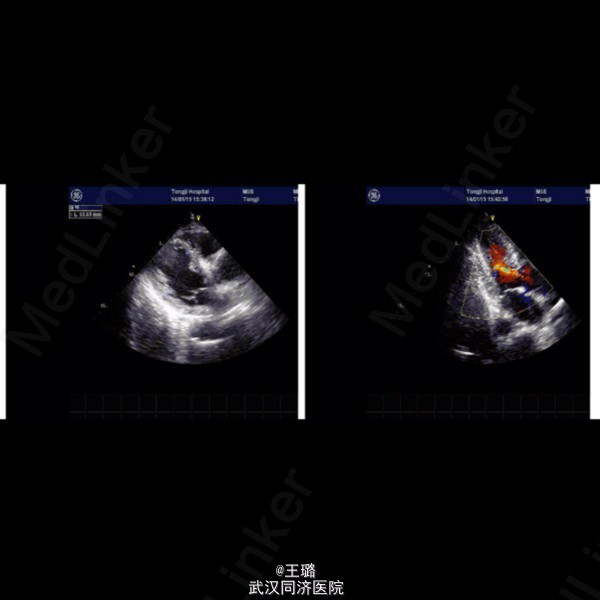

患者,男,62岁,一年前发现尿频、尿急,尿痛,近期出现血尿,遂来我院;B超示双肾结石,左侧多发囊肿,肾萎缩;心脏B超示左心室扩大,主动脉瓣退行性病变。考虑患者自身情况,目前未进行手术治疗。